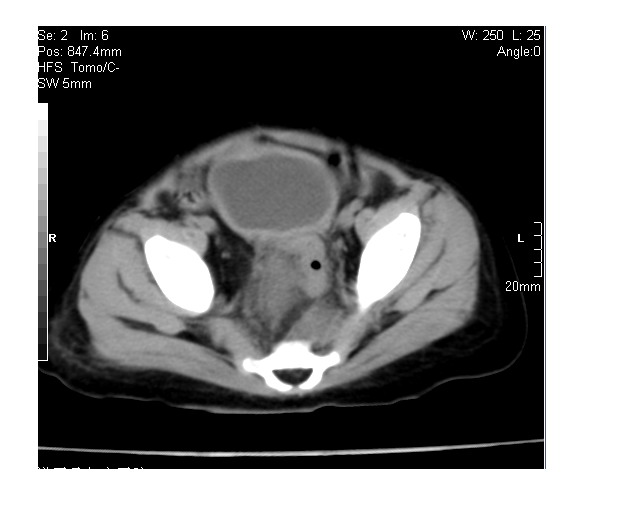

以下是引用lkc8963在2008-3-16 12:49:00的发言:[br]盆底巨大混杂密度肿块,富含多种组织成分包括脂肪/液体/软组织/钙化,边界清楚,向前压迫肠管及膀胱,向后突入骶尾部皮下脂肪层,首先考虑畸胎瘤,诊断时需要与脊柱裂/囊性淋巴管瘤等区别。